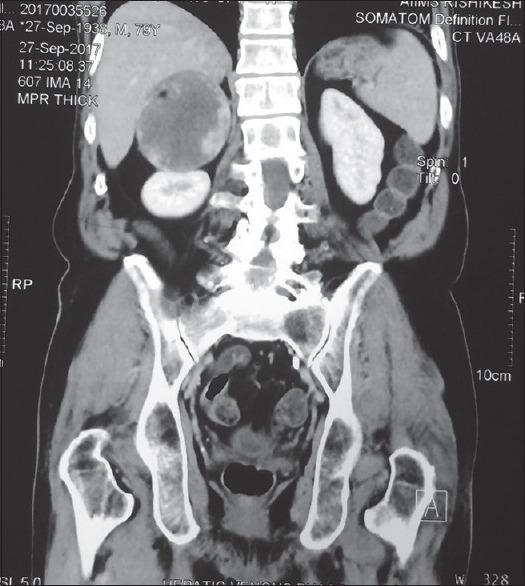

肾上腺海绵状血管瘤是一种罕见、良性、内分泌无活性的肿瘤。它们表现为肾上腺偶发瘤,大多无症状,但患者可能有腹痛。手术是治疗的主要手段。

Cavernous hemangiomas of the adrenal gland are rare, benign, endocrinologically inactive tumors. They present as adrenal incidentalomas, mostly asymptomatic, but patients may have abdominal pain. Surgery is the mainstay of treatment.